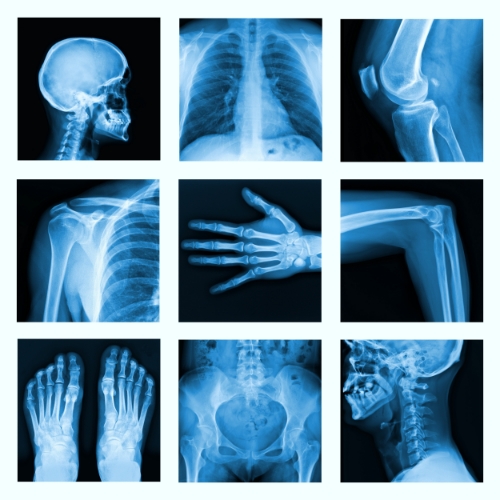

Unknown to many, the Doctoral level physical therapists‘ at The Fitness LAB are licensed to order many types of medical imaging. Imaging is a useful resource for musculoskeletal conditions and is an invaluable tool for Medical Professionals when used appropriately. Imaging such as MRI, X-ray, CT scans, and bone scans are prime examples of practical diagnostic imaging that facilitates accurate diagnosis, prognosis, intervention, and assessment of injuries and dysfunctions that the physical therapists at The Fitness LAB address on a daily basis.